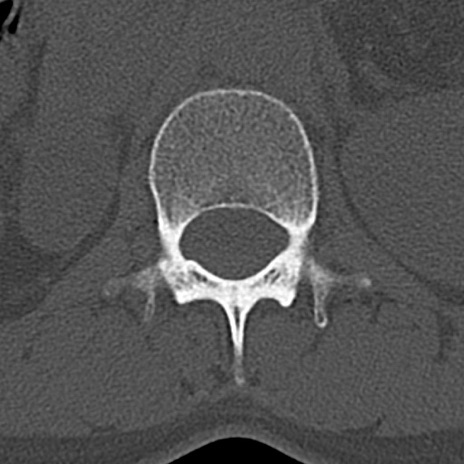

腰椎CT

横断像と矢状断像